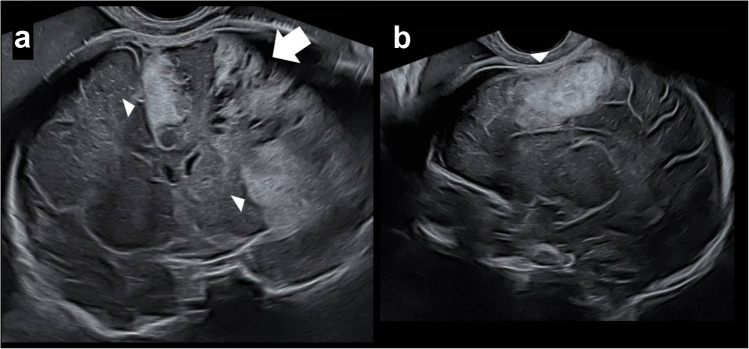

脑膜下出血是一种罕见的颅内出血,通常发生在新生儿身上。我们报告了一名28岁初产妇的首次产前诊断,胎儿磁共振成像(MRI)通过其特征皮质向内凹陷(“皮质屈曲”)和表观扩散系数图上的扩散受限来确定其脑膜下出血,后来通过尸检证实。本病例提示腹膜下出血的发病机制是胎儿的内在因素,而不是出生创伤或新生儿窒息,并强调了胎儿MRI在区分腹膜下出血和其他胎儿出血方面的关键作用,对产前咨询和围产期管理具有重要意义。

Subpial hemorrhage is a rare intracranial hemorrhage typically described in neonates. We report the first prenatal diagnosis of subpial hemorrhage in a 28-year-old primigravida, defined on fetal magnetic resonance imaging (MRI) by its hallmark cortical inward depression ("cortical buckling") and restricted diffusion on the apparent diffusion coefficient map, and later confirmed by autopsy. This case implicates intrinsic fetal factors-rather than birth trauma or neonatal asphyxia-in subpial hemorrhage pathogenesis and highlights the critical role of fetal MRI in distinguishing subpial hemorrhage from other fetal hemorrhages, with important implications for prenatal counseling and perinatal management.